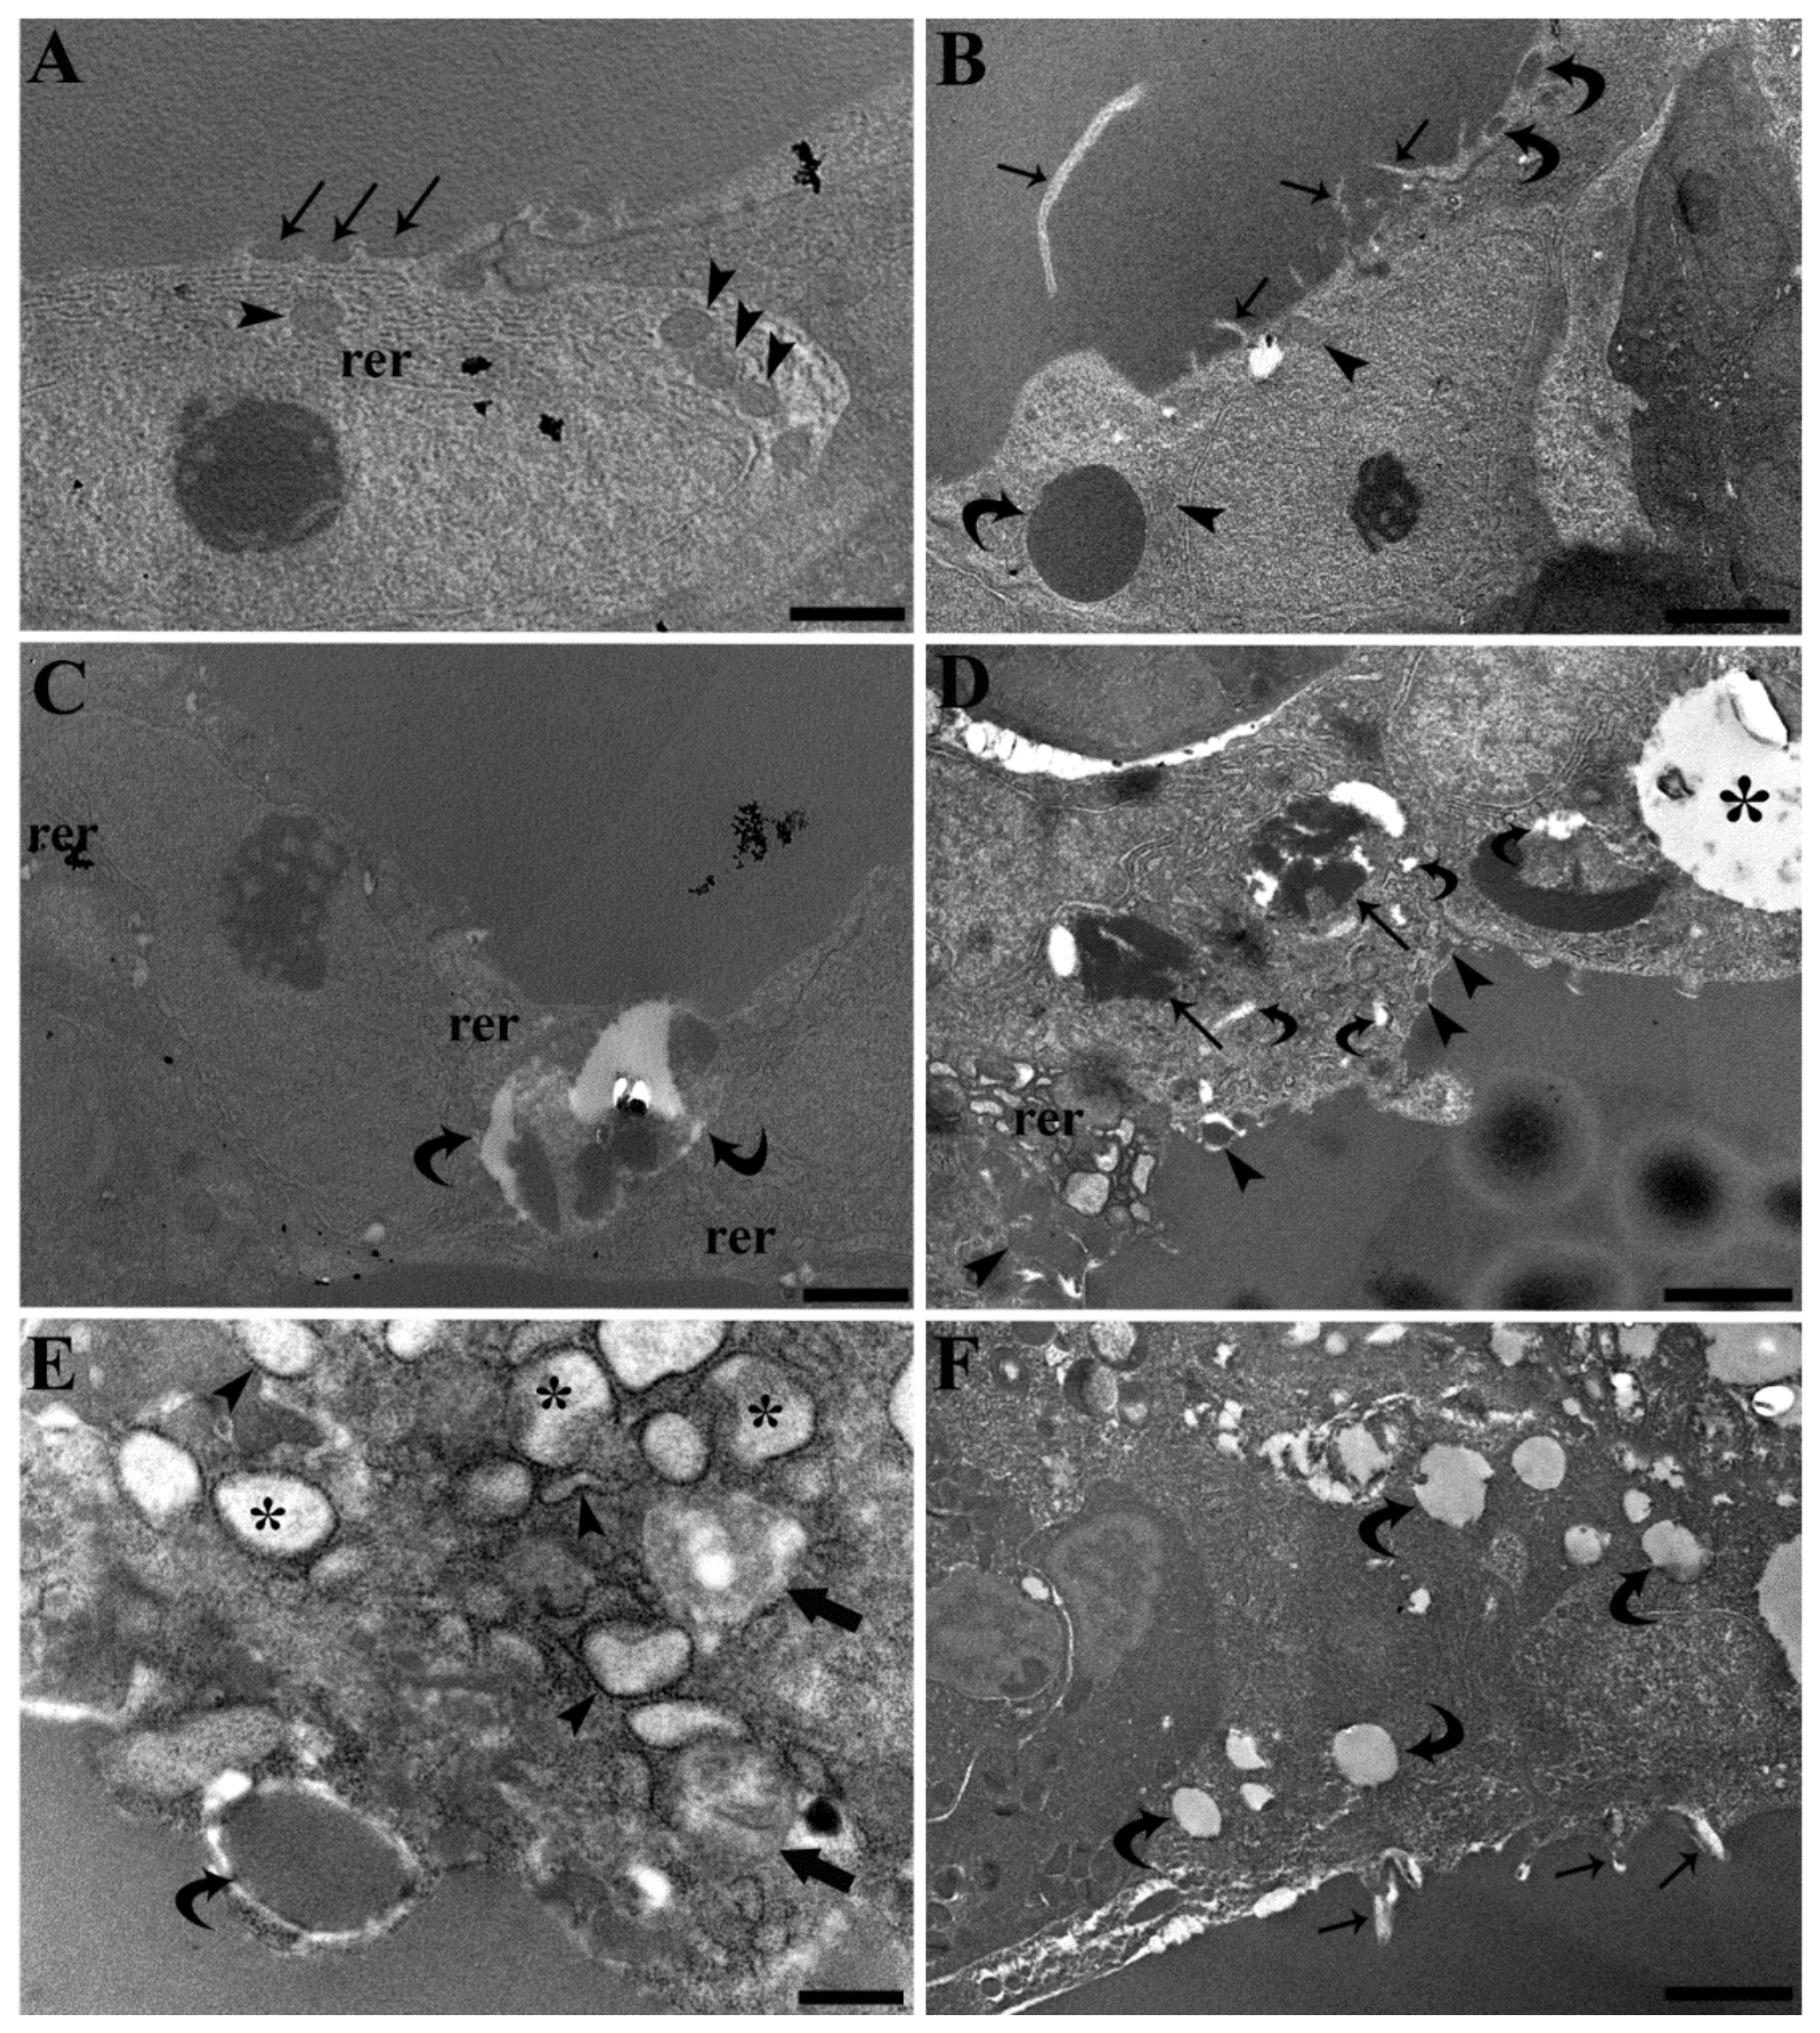

3.3. Follicle Ultrastructure

- Sakai, Y.; Yamashina, S.; Furudate, S.I. Missing secretory granules, dilated endoplasmic reticulum, and nuclear dislocation in the thyroid gland of rdw rats with hereditary dwarfism. Anat. Rec. 2000, 259, 60–66. [Google Scholar] [CrossRef]

- Schröder, M.; Kaufman, R.J. ER stress and the unfolded protein response. Mutat. Res. Fundam. Mol. Mech. Mutagen. 2005, 569, 29–63. [Google Scholar] [CrossRef]

- Manera, M.; Dezfuli, B.S.; Castaldelli, G.; De Pasquale, J.A.; Fano, E.A.; Martino, C.; Giari, L. Perfluorooctanoic Acid Exposure Assessment on Common Carp Liver through Image and Ultrastructural Investigation. Int. J. Environ. Res. Public Health 2019, 16, 4923. [Google Scholar] [CrossRef] [Green Version]

- Yan, S.; Zhang, H.; Wang, J.; Zheng, F.; Dai, J. Perfluorooctanoic acid exposure induces endoplasmic reticulum stress in the liver and its effects are ameliorated by 4-phenylbutyrate. Free Radic. Biol. Med. 2015, 87, 300–311. [Google Scholar] [CrossRef]

- Hocevar, S.E.; Kamendulis, L.M.; Hocevar, B.A. Perfluorooctanoic acid activates the unfolded protein response in pancreatic acinar cells. J. Biochem. Mol. Toxicol. 2020, 34, e22561. [Google Scholar] [CrossRef]

- Schmidt, F.; Wolf, R.; Baumann, L.; Braunbeck, T. Ultrastructural Alterations in Thyrocytes of Zebrafish (Danio rerio) after Exposure to Propylthiouracil and Perchlorate. Toxicol. Pathol. 2017, 45, 649–662. [Google Scholar] [CrossRef] [PubMed] [Green Version]

- Medelros-Neto, G.; Kim, P.S.; Yoo, S.E.; Vono, J.; Targovnik, H.M.; Camargo, R.; Hossain, S.A.; Arvan, P. Congenital hypothyroid goiter with deficient thyroglobulin: Identification of an endoplasmic reticulum storage disease with induction of molecular chaperones. J. Clin. Investig. 1996, 98, 2838–2844. [Google Scholar] [CrossRef] [PubMed]

- Néve, P.; Dumont, J.E. Time sequence of ultrastructural changes in the stimulated dog thyroid. Z. für Zellforsch. und Mikrosk. Anat. 1970, 103, 61–74. [Google Scholar] [CrossRef] [PubMed]

- Smith, C.J.; Gordon Grau, E. Ultrastructural changes in the parrotfish thyroid after in vitro stimulation with bovine thyrotropin. Fish Physiol. Biochem. 1986, 1, 153–162. [Google Scholar] [CrossRef]

- Nilsson, M.; Mölne, J.; Jörtsö, E.; Smeds, S.; Ericson, L.E. Plasma membrane shedding and colloid vacuoles in hyperactive human thyroid tissue. Virchows Arch. B Cell Pathol. Incl. Mol. Pathol. 1988, 56, 85–94. [Google Scholar] [CrossRef]

- Cheville, N. Ultrastructural Pathology: The Comparative Cellular Basis of Disease, 2nd ed.; Wiley-Blackwell: Ames, IA, USA, 2009; ISBN 9780813803302. [Google Scholar]

- Manera, M.; Castaldelli, G.; Fano, E.A.; Giari, L. Perfluorooctanoic acid-induced cellular and subcellular alterations in fish hepatocytes. Environ. Toxicol. Pharmacol. 2021, 81, 103548. [Google Scholar] [CrossRef]